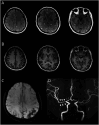

Figure 1. Visualization of Blood-Brain Barrier Disruption in a Patient With Reversible Cerebral Vasoconstriction Syndrome

(A) Diffuse contrast medium extravasation was demonstrated by 3-dimensional contrast-enhanced T2-weighted fluid-attenuated inversion recovery images, suggesting blood-brain barrier disruption. (B) T1-weighted images showed no abnormal signals within the cortical sulci. (C) This patient was complicated by convexity subarachnoid hemorrhage, as shown by susceptibility-weighted angiography images. (D) Magnetic resonance angiography revealed long-segmental (white arrowheads) and focal (black arrowheads) vasoconstrictions.